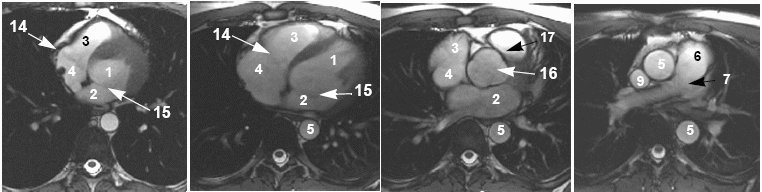

Cardiac anatomy

View an image plane and refer to the legend below for the corresponding cardiac anatomy.

| Cardiac anatomy image legend | |||

|---|---|---|---|

| 1 = left ventricle

2 = left atrium 3 = right ventricle 4 = right atrium | 5 = aorta

6 = pulmonary artery 7 = left pulmonary artery 8 = right pulmonary artery | 9 = superior vena cava

10 = inferior vena cava 12 = right pulmonary vein 13 = pulmonary valve | 14 = tricuspid valve

15 = mitral valve 16 = aortic valve 17 = ventricular outflow tract |